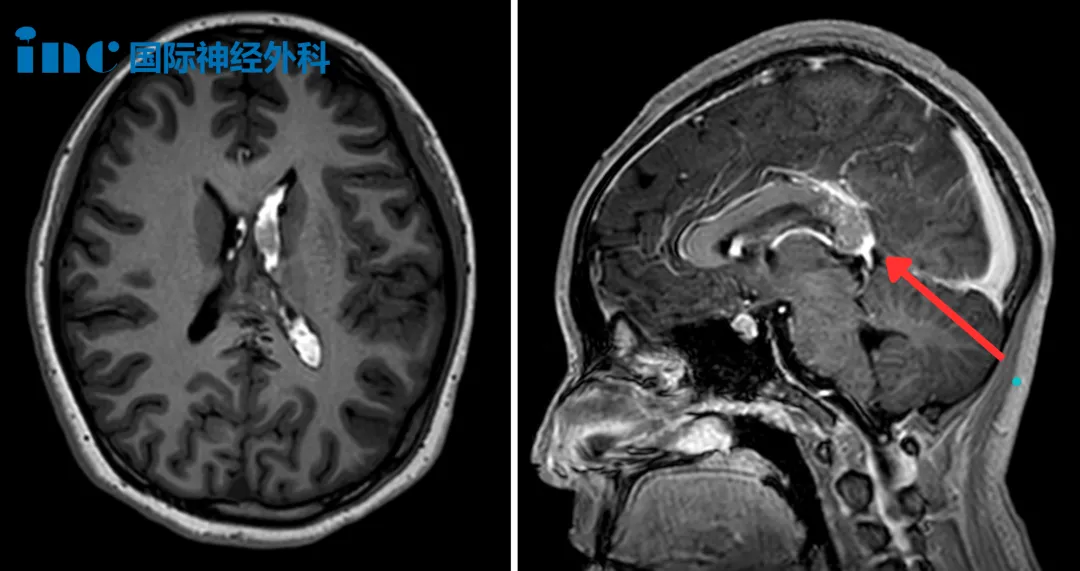

加班后身体一侧突然发麻,当查出可怕的脑干“肿瘤”,我花了4年才走上手术台

人生的道路虽然漫长,但紧要处常常只有几步。没有一个人的生活道路是笔直的,没有岔道的。走错一步,就可以影响人生的一个时期,也可以影响一生。 作家柳青 2021年,在经历4年的反复权...